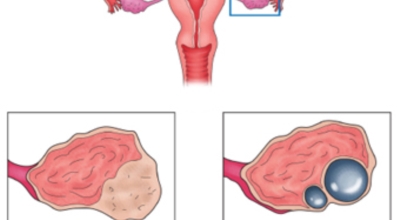

난소낭종이란 난소에 발생되는 물혹이지요. 안에는 그냥 수액이나 장액이지만, 혈액일 수도 있으며, 지방이나 농양일 수도 있어요. 이 난소낭종은 없어졌다 생겼다 하는 기능성 낭종과 점점 커지는 악성 낭종으로 나뉘는데요. 주로 악성 낭종이 문제일 것이라고 생각하지만 기능성 낭종도 커지면 터지면서 사람을 응급실로 실려가게 만들어요.

난소 낭종의 종류

기능성 낭종 : 배란 낭종이라고도 하며 보통은 증상을 유발하지 않는 가장 흔한 종류의 낭종이지요. 그들은 난포 낭종 ( 난포에서 발생, 난소의 작은 주머니) 및 황체 낭포(난포가 난자를 방출한 후 발생)로 형성될 수 있어요.

유피종 및 기형종 : 태어날 때 부터 존재하며 머리카락, 뼈, 치아 및 피부와 같은 다른 조직을 포함합니다. 여성의 십만 명에 열명 정도가 이러한 유형의 낭종이 있는 것으로 추정되는 비교적 드문 경우이지요 .

낭종: 난소 표면에 형성되며 난소의 체액이나 일부 조직으로 채워져 있어요.

자궁내막증 : 이것은 자궁 외부 조직에서 자자고 혈액으로 가득 찬 낭종이지요.